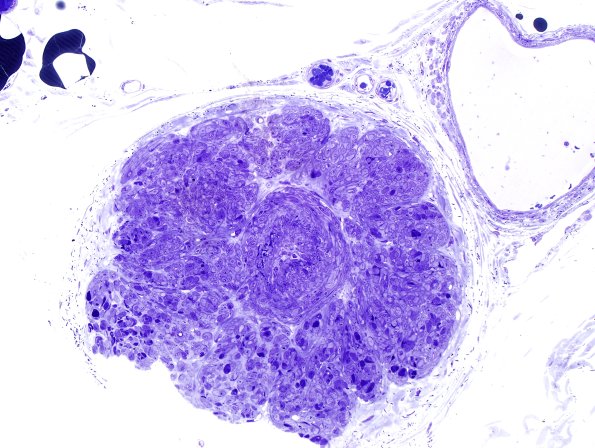

Washington University Experience

VASCULAR

Hypoxia-Ischemia, fetal-neonatal

White Matter